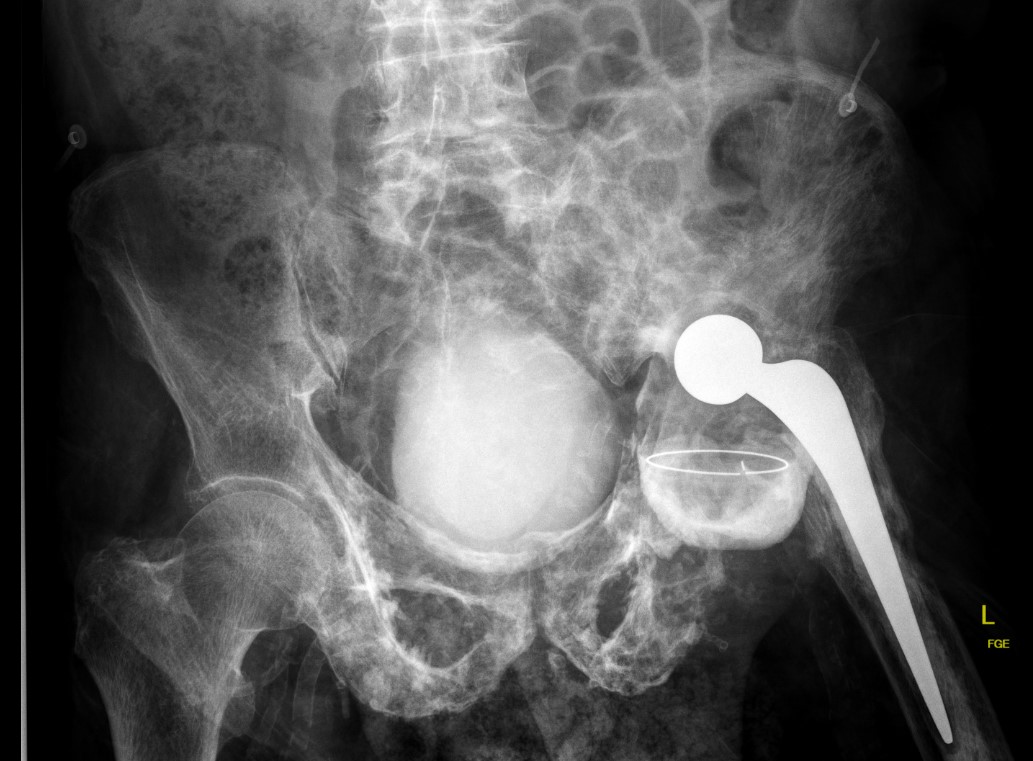

Pelvis

Coxa vara / protrusio / OA

Hip osteoarthritis with coxa vara and protrusio

Acetabulum

- difficult reaming due to hard bone

- protrusio - consider medial bone graft / cages / lateral offset liners

- limited ability for cement interdigitation - uncemented cups may be preferrred